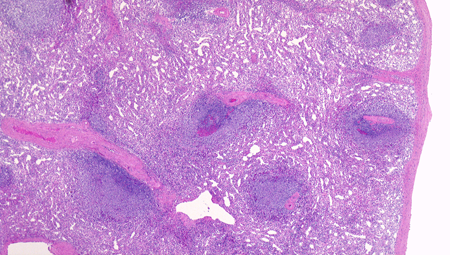

白脾髄の構造

spleenA011.jpg

白脾髄, 辺縁帯/周辺帯は脾臓のリンパ装置として機能する. 開放性末梢血管流床を介して伝達される免疫情報はこれらのリンパ装置で処理され効率よく免疫反応がおこる.

白脾髄 white pulpは中心動脈周囲に形成されているリンパ組織で, 動脈周囲リンパ鞘 periarteriolar lymphoid sheath(PALS)とリンパ濾胞(lymph follicles)の異なる2つの領域が識別される.

脾動脈脾柱という結合組織を通って実質内に入るところから毛細血管に至るところまで、その周囲にリンパ鞘(リンパ鞘=PALS/ peri-arterial lymphatic sheathの略)が形成され、所々にリンパ濾胞が発達している. 濾胞内には胚中心が見られることが多い。胚中心の周りには暗調にそまる小型のリンパ球がマントル層を作って取り囲む。リンパ鞘もリンパ節の構造と同じく粗で不規則な細網線維からできたネットワークが骨格となっている。

リンパ鞘はT細胞領域リンパ濾胞はB細胞由来です。PALSのT-cellsはCD4+ cell > CD8+ T-cells

PALS, 動脈周囲リンパ鞘 periarteriolar lymphoid sheath

リンパ濾胞

辺縁帯/周辺帯 Marginal zone

胚中心が多数出現しているときはなんらかの抗原刺激を受けたと考えられる.

慢性感染症がある人の脾臓や特発性血小板減少性紫斑病の人の脾臓では胚中心が特に発達している. 一方で自己免疫性溶血性貧血では胚中心は少なく、先天性球状赤血球症ではほとんど見られない.